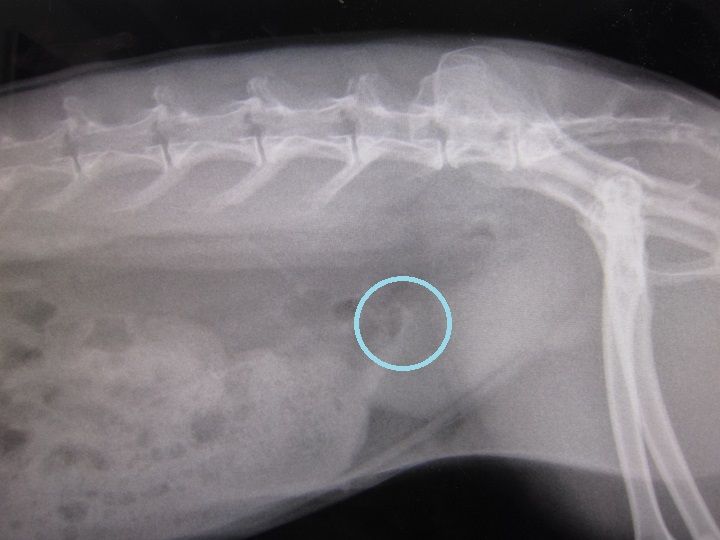

ただ、強いてこじつけレベルで指摘するとしたら…こうゆう白い塊ね。

kagu0811

これは左右対象にあるから恐らく乳頭と思われる… それと、

kagu0810

…印付けに自信がないですが、薄いおはじきのような白色は写ってます。

上にいくと消化器官ですが、丸くなる手前かも、とかとか…

…ちょっとモヤっと感は残るんですが、

「喜んでも良いと思います」て言うてたから、喜んでいいんやと思います(^-^;)